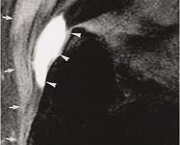

A bursite Trocanteriana é uma inflamação em uma ou mais bursas encontradas na articulação do quadril. Esta bursite pode ser causada por uma queda ou golpes ao lado do quadril, atrito associado a uso excessivo, pé pronado ou fraqueza de glúteo médio.

Um destes fatores presentes gerará a inflamação e consequente dor durante uma corrida, desajuste no andar da pessoa ou crepitação na articulação. O tratamento deve ser realizado conforme a causa da doença, por exemplo, se for por fraqueza de glúteo, deve-se fortalecer glúteo.